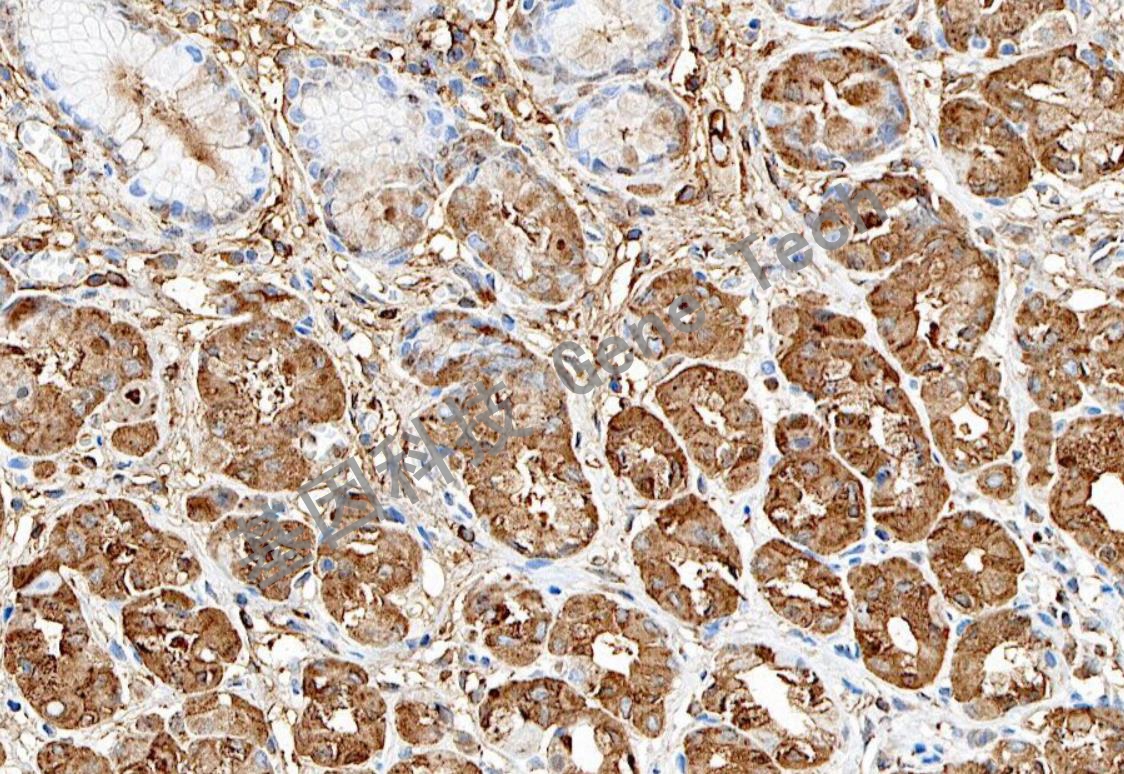

| 預處理:高pH熱修復 | 陽性位置:細胞漿 | 陽性對照:胃癌 |

| 胃底腺石蠟切片,用 Pepsinogen I(GT2463)染色,細胞漿陽性,DAB 顯色。 | ||